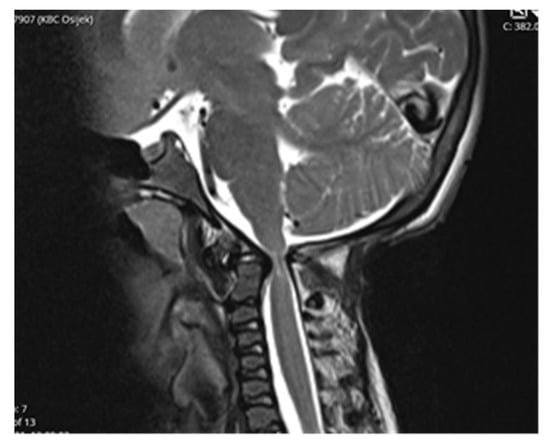

Computed tomography (CT) scan of cranio-cervical junction revealed bifid arch of the atlas as a part of skeletal disorders. Additional preoperative magnetic resonance imaging (MRI) revealed a critical stenosis of cranio-cervical junction with concomitant myelopathy (Figure 3).

Follow-up MRI scan of cranio-cervical junction after three months and one year revealed residual stenosis of CCJ and myelopathy of cervical medulla. Nevertheless, the postoperative diameter of decompressed CCJ was insignificantly wider in the sagittal and axial planes compared to preoperative MRI scan (Figure 5).

A preoperative magnetic resonance imaging (MRI) scan revealed a severe myelopathy at the level of cranio-cervical junction and radiologic signs of atlanto-axial instability. Therefore, the authors decided to obtain only bone decompression of the foramen magnum and C1 vertebra to prevent any possible neurological deterioration with the aim of achieving a better radiologic outcome, e.g., partial or nearly complete regression of myelopathy. There were no radiological signs of platybasia and basilar invagination according to radiographic measurements of cranio-cervical junction.

Despite an adequate decompression of the CCJ, a postoperative follow-up MRI scan revealed only a limited widening of the diameter of the cranio-cervical junction caused by radiologically confirmed atlanto-axial instability. There was no sign of regression of myelopathy. The authors did not confirm the utmost benefit of surgery according to radiological follow-up.

Figure 3. Preoperative MRI scanning of cranio-cervical junction revealed critical stenosis and myelopathy, 14 years of age.